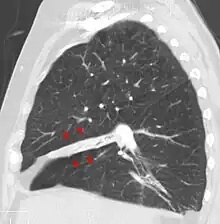

Atelectasis of the middle lobe on a sagittal CT reconstruction.

Atelectasis may be an acute or chronic condition. In acute atelectasis, the lung has recently collapsed and is primarily notable only for airlessness. In chronic atelectasis, the affected area is often characterized by a complex mixture of airlessness, infection, widening of the bronchi (bronchiectasis), destruction, and scarring (fibrosis).